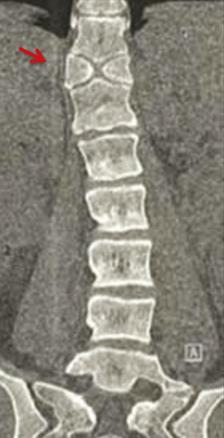

Une patiente de 25 ans, sans antécédents pathologiques particuliers, consulte pour des dorsolombalgies mécaniques avec une irradiation intercostale, sans déficit moteur ou sensitif. L’examen clinique met en évidence une hypercyphose dorsale et une hyperlordose lombaire. Les scanners dorsolombaires (fig. 1 et 2) objectivent une division complète du corps vertébral D11 en hémivertèbre dite « en aile de papillon ». La patiente est mise sous traitement symptomatique associé au renforcement des muscles paravertébraux et respiratoires avec une bonne évolution.

Les vertèbres papillon sont secondaires à un défaut de fusion du corps vertébral plus ou moins étendu au cours de l’embryogenèse.1 Cette anomalie du développement, qui implique généralement une seule vertèbre, peut induire une division complète du corps vertébral en deux hémivertèbres de forme triangulaire. Elles sont souvent asymptomatiques et détectées accidentellement.1 La concomitance entre les vertèbres papillon et les maladies congénitales telles que les syndromes d’Alagille, de Jarcho-Levin, de Crouzon et de Pfeiffer, est parfois constatée. En raison de leur rareté, elles peuvent facilement être confondues à tort avec d’autres processus pathologiques, notamment une fracture vertébrale.

La colonne vertébrale thoracolombaire est le site le plus fréquent pour la formation des vertèbres papillon.4,7,8 Le siège préférentiel d’une vertèbre papillon unique est T1 et T11.2,7